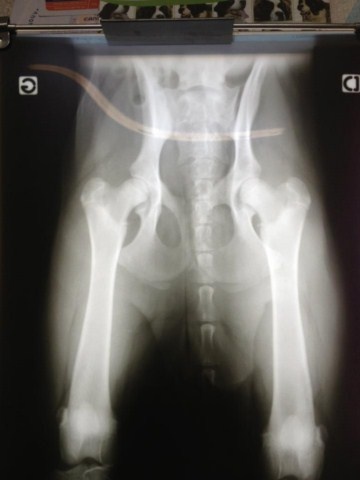

DYSPLASIE HANCHE

Le Berger Allemand ne présente pas de problèmes de santé particuliers, sa longévité est bonne. Si la dysplasie de la hanche frappe de nombreux chiens de taille moyenne à...